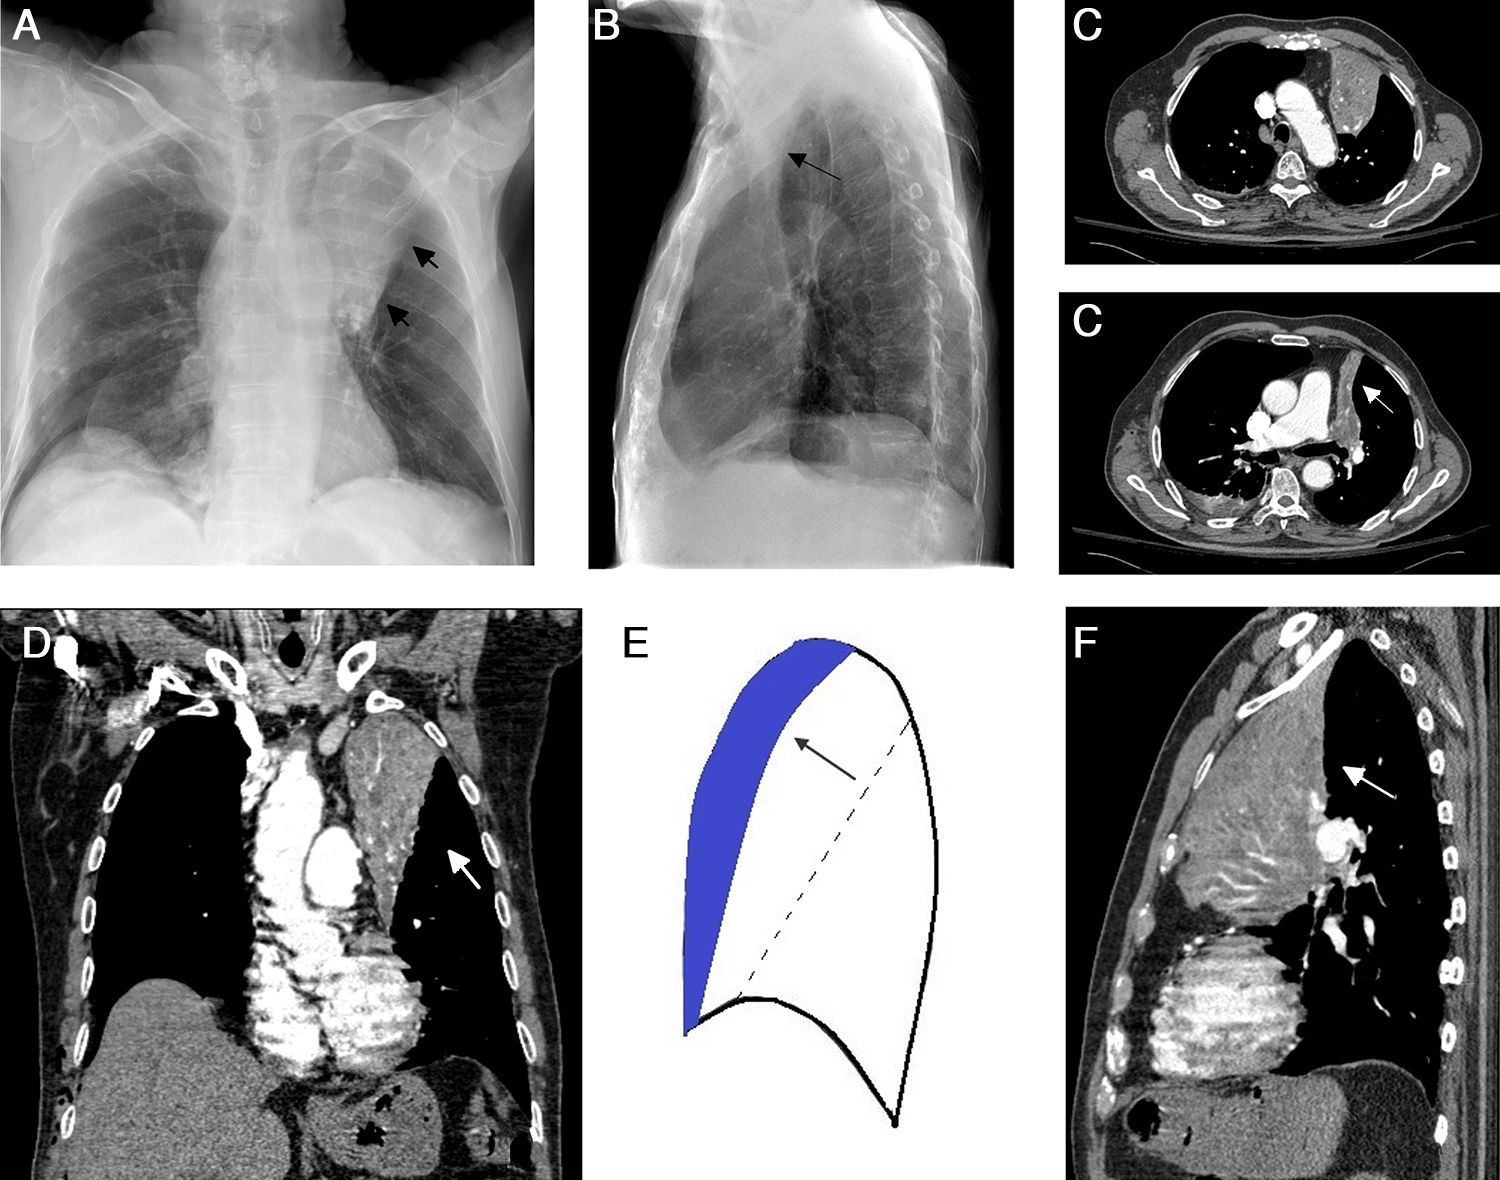

La atelectasia pulmonar es un indicador importante de una enfermedad subyacente, potencialmente grave, que es imprescindible diagnosticar precozmente. Uno de los mecanismos más frecuentes es la reabsorción de aire distal a la obstrucción de las vías respiratorias. La radiografía de tórax es una herramienta excelente para diagnosticarla, especialmente útil para descartar obstrucciones bronquiales centrales (por ejemplo, una neoplasia endobronquial). Si no se reconocen correctamente los signos de la pérdida de volumen el diagnóstico y el tratamiento pueden retrasarse. En este artículo se describen los principales hallazgos radiográficos de la atelectasia pulmonar lobular y su correlación con la tomografía computarizada. Se incluyen los signos clásicos descritos en la bibliografía y otros menos conocidos y a su vez sutiles.

Atelectasis is an important indicator of potentially severe underlying disease that must be diagnosed as early as possible. One of the most common mechanisms is the reabsorption of air distal to respiratory tract obstruction. The chest X-ray is an excellent tool to diagnose atelectasis, and it is especially useful for ruling out central bronchial obstructions (e.g., from endobronchial tumors). If the signs of volume loss are not recognized correctly, the diagnosis and treatment can be delayed. This article describes the main findings of lobar atelectasis on chest X-rays and their correlations with CT findings, including the classic signs described in the literature and other, less known and sometimes subtle signs.